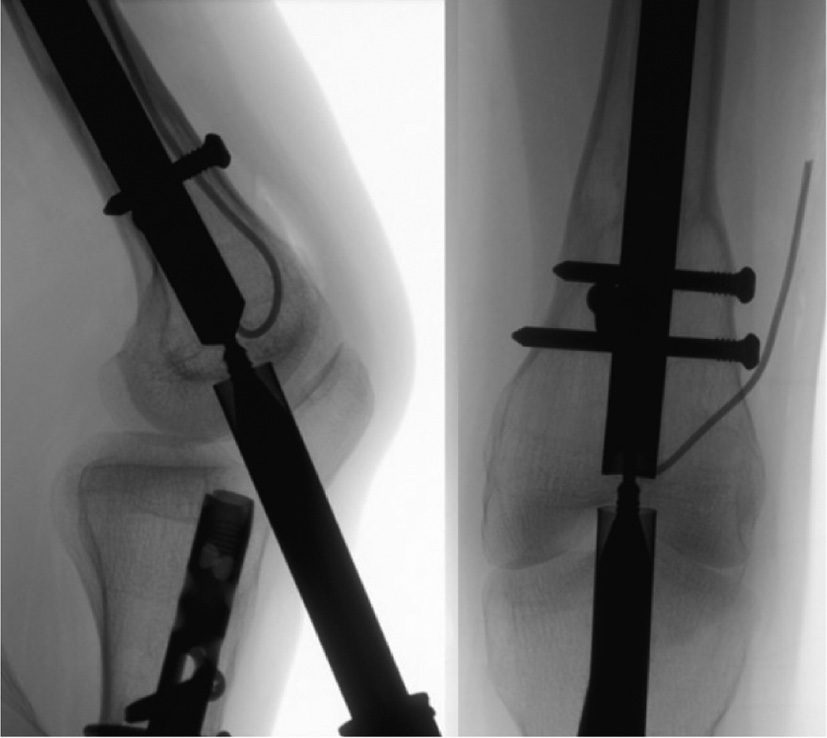

Figure 24. It is important that the guidewire is aligned perfectly to the center of the nail under fluoroscopy in both the coronal and sagittal planes.

jposna20220031_fig24.jpg